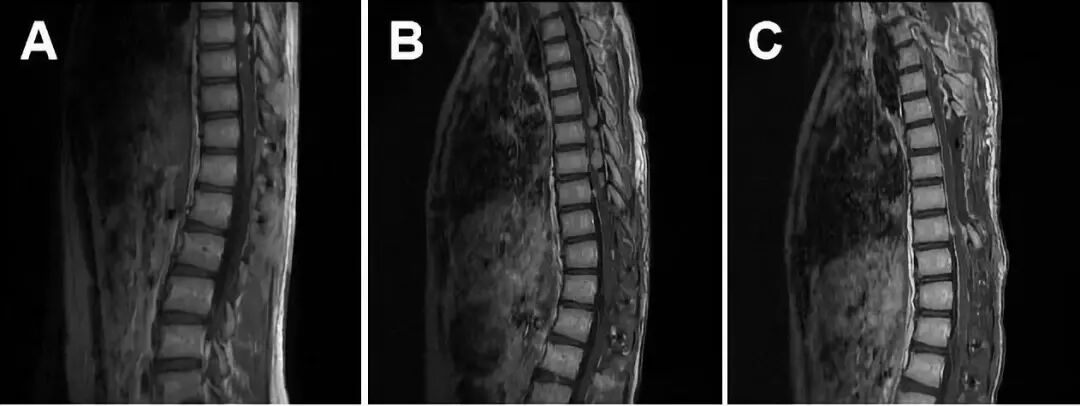

术后经康复科治疗后出院,当时建议患者行放疗,患者要求暂不放疗,予短期密切随访。术后两月(2018-06-06)复查增强MRI,未见原位复发及转移灶明显增大。术后9个月(2019-01-08)复查胸椎增强MRI提示:胸10-腰1椎体水平椎管内黏液乳头状室管膜瘤术后改变,原手术部位上方约胸7-9节段脊髓表面病灶对比前片(2018.06.06)病变增多增大,建议入院再次手术。

入院后查全脊柱及头颅增强MRI (2019-01-23)提示:所示颈椎管内脊髓表面、脑干前方、四脑室后缘及小脑半球表面等部位的原有多发强化灶对比前片(2018-04-07)未见明显进展。 决定于2019-01-23全麻下行[胸6-8]椎管内病损切除术+[胸6-8]椎管减压术。术中全椎板切除胸6-8椎板及棘突,切开硬脊膜及蛛网膜后,见多发肿瘤,较大者有3枚,大小约3cm*1cm*1cm、2cm*1cm*1cm,1cm*1cm*1cm,呈灰红色,血供一般,质地稍韧,包绕神经根,部分侵袭突破软膜侵袭髓内,与脊髓边界欠清,沿相对边界尽量切除肿瘤达次全切除,缝合硬膜,去椎板减压。术后背部切口愈合可,四肢肌力Ⅴ级,肌张力正常,双下肢膝关节以下触觉减退,病理征阴性。

图4. A: 术后2月复查(2018-06-06)未见局部复发及转移灶明显增大;B: 术后9月复查(2019-01-08)见胸6-8水平椎管内转移灶明显增大,建议入院行手术治疗;C: 第二次术后复查(2019-01-25)切除胸6-8水平椎管内肿瘤,未见明显肿瘤残留。